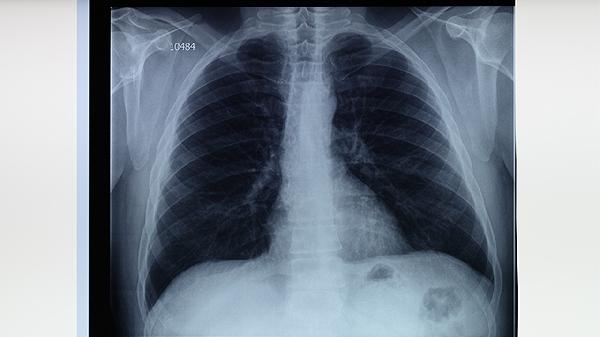

治疗期间每月需进行痰涂片检查,每2个月拍摄胸部X线片。肝功能异常是常见药物副作用,应定期检测转氨酶指标。治愈后仍需每年随访1次,持续观察3年以排除复发可能。